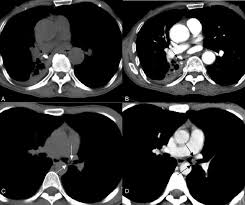

Chondromesenchymal Hamartomas In A 24 Year Old Male Mimicking A Posterior Mediastinal Tumor And A 5 Month Old Boy With Postoperative Disseminated Intravascular Coagulation Two Case Reports Diagnostic Pathology Full Text

Chondromesenchymal Hamartomas In A 24 Year Old Male Mimicking A Posterior Mediastinal Tumor And A 5 Month Old Boy With Postoperative Disseminated Intravascular Coagulation Two Case Reports Diagnostic Pathology Full Text from media.springernature.com